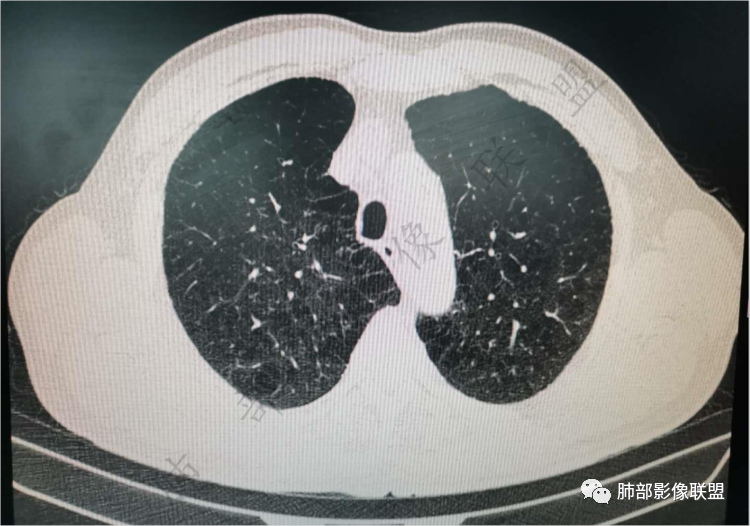

肺气肿背景

老年男性,肺气肿背景,右肺上叶前段胸膜下结节,部分边缘毛糙,血管集束增粗,支气管似有截断,胸膜牵拉,结节密度不均,两个月随访结节有增大,考虑恶性,肺癌可能;另右肺上叶后段肋胸膜区小片状类结节影,考虑炎性可能。

支气管变形、壁增厚,提示慢性支气管炎症

边缘平直

宽基底与胸膜相连,附近胸膜增厚,糊墙

还是支持炎性放前面,恶性待排